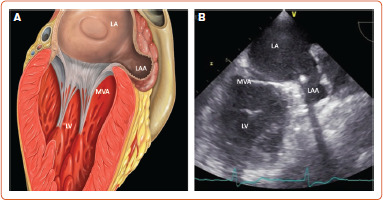

非瓣膜性房颤是一种常见的临床疾病,与血栓栓塞并发症的风险增加有关。因此,口服抗凝治疗(OAT)是非瓣膜性房颤治疗的基石。尽管OAT具有公认的疗效,但由于出血或出血风险高,许多患者无法接受这种预防性治疗。90%以上的血栓形成于左心耳,这一事实促使人们开发了降低栓塞风险的替代方法。左心耳封堵术(LAAO)是一种非药物选择,用于预防OAT禁忌症的非瓣膜性房颤患者的心脏栓塞事件。对LAAO手术的需求呈指数级增长,临床医生在管理有OAT禁忌症的患者时应考虑这种替代方案。本综述总结了当前对LAAO的思考。

Non-valvular AF is a common clinical condition associated with an increased risk of thromboembolic complications. As a consequence, oral anticoagulant therapy (OAT) is the cornerstone of non-valvular AF management. Despite the well-established efficacy of OAT, many patients cannot receive this preventive therapy due to bleeding or a high risk of bleeding. The fact that more than 90% of thrombi are formed in the left atrial appendage has led to the development of alternative methods to reduce the embolic risk. Left atrial appendage occlusion (LAAO) is a non-pharmacological option for preventing cardioembolic events in patients with non-valvular AF with a contraindication to OAT. The demand for LAAO procedures is growing exponentially and clinicians should consider this alternative option when managing patients with a contraindication to OAT. This review summarises the current thinking about LAAO.